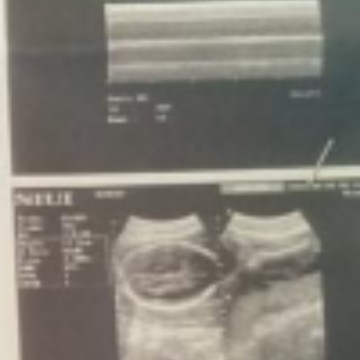

felvic ultrasound

Hi mga mom's cnu s inyo nkaranas NG 1st ultrasound n di nkita gender NG baby 29 weeks aq nag pa ultrasound Sabi suhi c baby and nakadapa p cya Kya d nkita gender nya another ultrasound ulit Sana this coming months ok n position nya at Sana di n cya nkdpa para makita n if boy or girl #Team November #31 weeks and 2 days